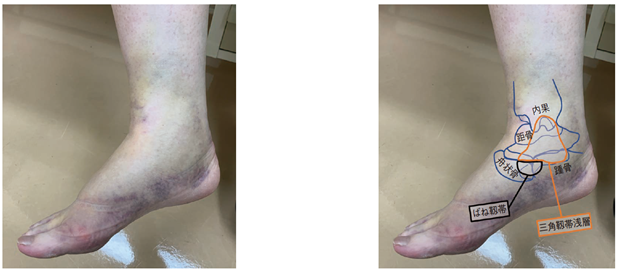

回内捻挫

三角靱帯や遠位脛腓靱帯が損傷しやすいとされています。

(図11) 整形外科Surgical Technique vol.12 no.6 2022 104-110 足の捻挫で起こること 治療戦略と手術テクニック⑤ 足関節内側靱帯損傷 天羽健太郎 抜粋引用

背屈,外転,外がえしからなる複合運動の負荷によって生じ,三角靱帯(浅層・深層)損傷や遠位脛腓靱帯の前下脛腓靱帯損傷(下図)が発生しやすいです。

図3 整形外科Surgical Technique vol.12 no.6 2022 104-110 足の捻挫で起こること 治療戦略と手術テクニック⑤ 足関節内側靱帯損傷 天羽健太郎 より抜粋